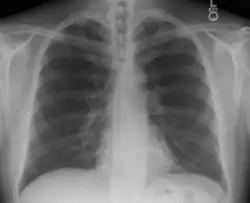

Example images are useful to help you to explain why one technique is better than another. |